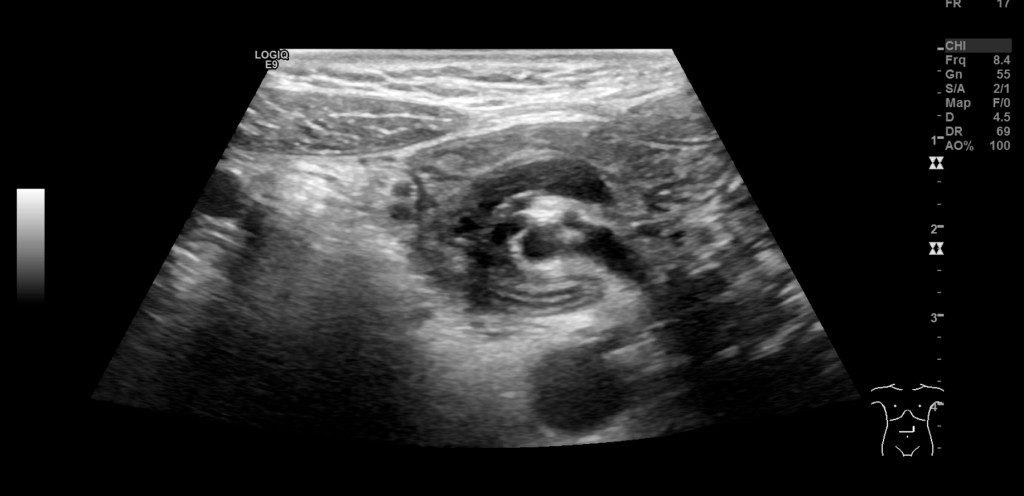

The girl was kept under observation throughout the weekend. Her general condition had improved, and she had little abdominal pain and no episodes of vomiting. Her electrolyte levels quickly normalised following initiation of fluid therapy. On Monday morning, an ultrasound examination was performed by an experienced paediatric radiologist who confirmed the whirl sign (Figures 1 and 2) and who suspected concomitant volvulus (where a loop of intestine twists about its own axis). The diagnosis was confirmed by an upper gastrointestinal series, which showed passage of contrast to the proximal small intestine, but no further (Figure 3). The transition between the duodenum and small intestine was just to the left of the midline, caudal to the level of the duodenal bulb, which suggested malrotation with volvulus. The explanation for the patient's long-term symptoms had finally been found (Figure 4).

Figure 2 Ultrasound. Whirl sign involving mesenteric vessels and loops of small intestine. The superior mesenteric artery …

Figure 2 Ultrasound. Whirl sign involving mesenteric vessels and loops of small intestine. The superior mesenteric artery (red Doppler signal) is to the right of the superior mesenteric vein (blue Doppler signal).

Upon ultrasound examination, the superior mesenteric vein can usually be seen to the right of the superior mesenteric artery. If the vein is to the left or in front of the artery, this should raise strong suspicion of malrotation. Sensitivity is reported to be 67–100 % and specificity 83–92 % (7). If abnormal positioning is detected with ultrasound, an upper gastrointestinal series should then be performed. In our patient, ultrasound revealed the 'whirl sign', which is considered 100 % specific for midgut volvulus (7): the duodenum, the proximal portion of the small intestine, and the superior mesenteric vein twist around the superior mesenteric artery. The underlying cause is malrotation and a short mesentery. Midgut volvulus gives rise to a duodenal – i.e. proximal – obstruction, and abdominal x-ray may thus be completely normal, despite the child having an acute condition in need of surgical intervention.